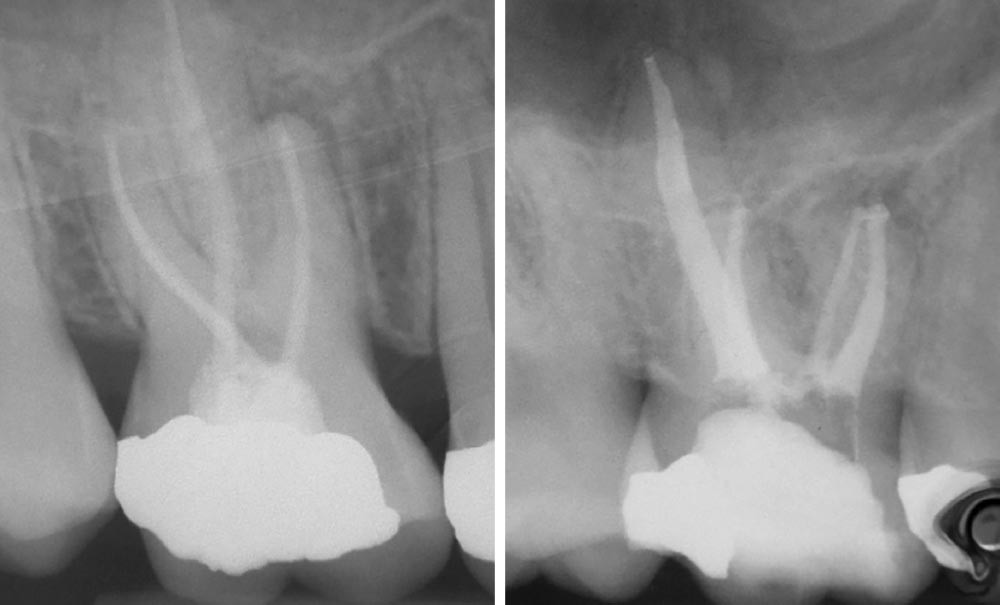

Selon l’IASP (International Association for the Study of Pain), le mécanisme de la douleur varie selon le stimulus ou le type de lésion (fig. 1).